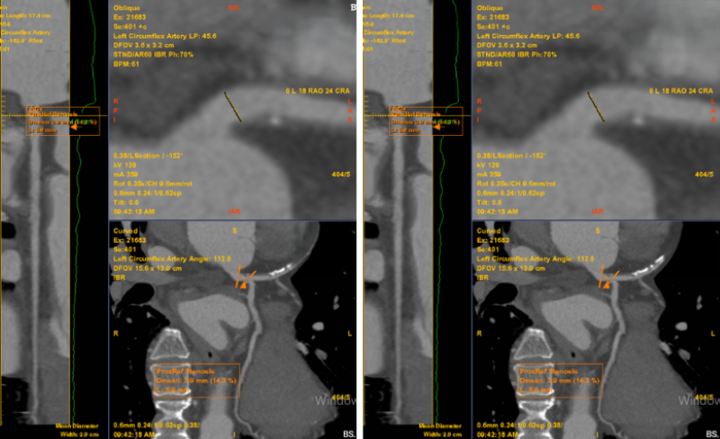

Nhận định cơn đau ngực có nhiều khả năng liên quan đến bệnh lý mạch vành, các bác sĩ đã chỉ định chụp MSCT mạch vành. Kết quả cho thấy bệnh nhân có mảng xơ vữa hỗn hợp gây hẹp khoảng 60–70% đoạn LAD1–2, được phân loại CAD-RADS 3.

Chỉ đau tức ngực trái thoáng qua, không ngờ phát hiện bệnh lý tim mạch nguy hiểm- Ảnh 1.

Bất thường được phát hiện trên phim chụp MSCT mạch vành của bệnh nhân (Ảnh: Medlatec).